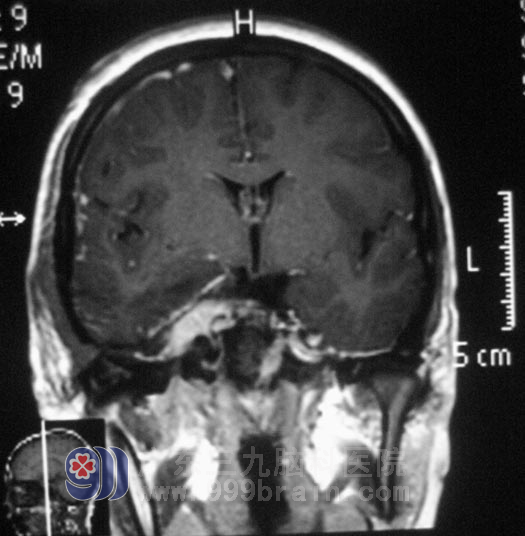

小李在2008年高考那年,出现右眼视力下降,以为是高负荷的复习迎考,造成视力出现问题。一年前右耳听力开始进行性下降,前十多天又出现了右耳失聪,外院行头颅MR检查提示:右侧眶内、中颅窝底、岩斜区占位,病变大小4.98cm×3.34cm×2.62cm,主要位于中颅窝,小部分累及后颅窝,脑干受压。

广东三九脑科医院综合神经外科 鲁明主任查阅影像资料发现:肿瘤侵润海绵窦,颅内外沟通,经CT检查见蝶骨及斜坡右侧、右侧颞骨岩部、额骨底部右侧骨质异常,经耳鼻喉科活检排除鼻咽癌。